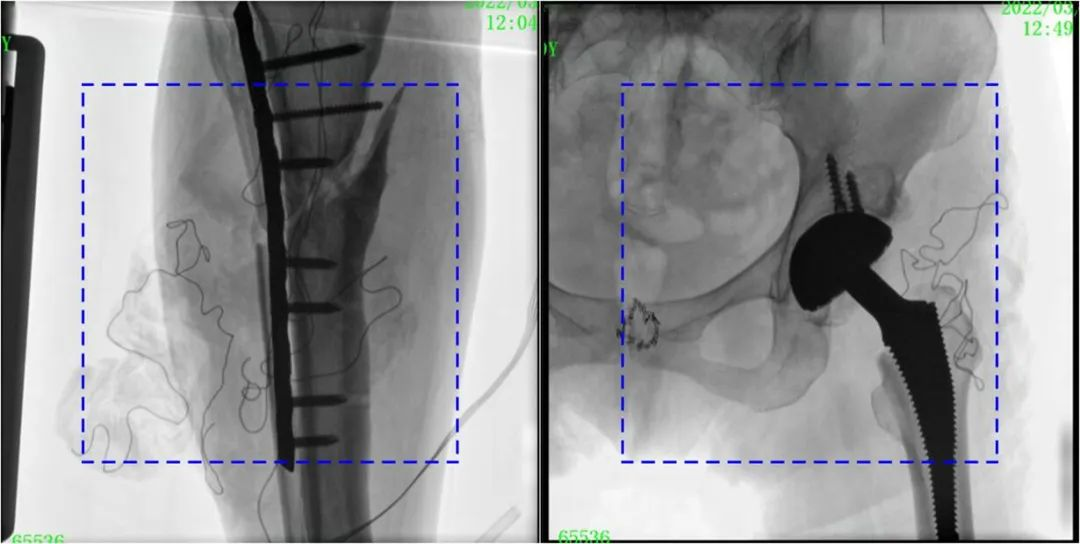

與傳統(tǒng)的21CM×21CM成像尺寸相比,普愛醫(yī)療大平板一體式C形臂具有30CM×30CM更大成像尺寸,能夠一次成像5.5節(jié)椎體,呈現(xiàn)更全面的影像信息,即便是手術(shù)經(jīng)驗(yàn)不豐富的年輕醫(yī)生也能通過(guò)圖像迅速判斷椎體節(jié)段、定位手術(shù)部位,避免因?yàn)橐曇安蛔愣斐傻亩啻味ㄎ?、反?fù)曝光,提高效率的同時(shí)避免過(guò)量攝入輻射。

普愛醫(yī)療大平板一體式C形臂圖像與傳統(tǒng)圖像對(duì)比(藍(lán)色虛線內(nèi)為傳統(tǒng)21CM×21CM平板的成像區(qū)域)